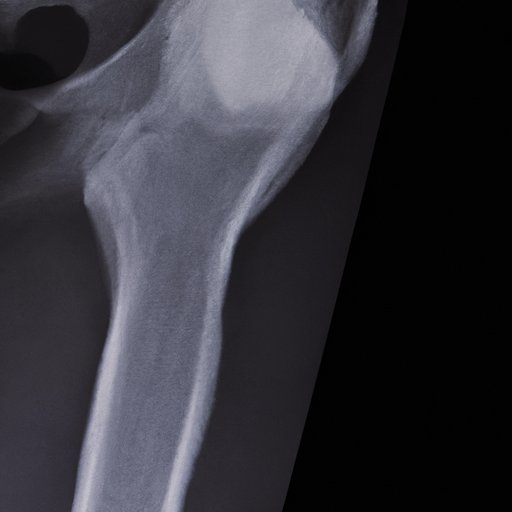

Definition of Bone Scan

A bone scan is a medical imaging technique that uses radioactive tracers to assess the overall health of bones in your body. The radioactive substance is injected into your bloodstream and accumulates in areas of high bone activity. The scan captures images of the radioactive material, and a computer generates a picture of the bones in your body.

Bone scans differ from other imaging tests like X-rays, CT scans or MRI scans. X-rays provide a clear picture of the bones but do not show bone activity. CT scans and MRI scans provide more detailed images but are not effective in detecting bone activity like bone scans.

Bone scans work by detecting radioactive tracers that accumulate in areas of high bone activity. Areas of high bone activity could occur due to fractures, infections, inflammation, or cancer. The radiation emitted by the radioactive tracer is captured by a gamma camera and is used to generate detailed images of the bones.